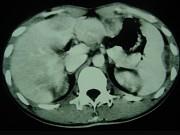

问题 男,35岁,病人低热、消瘦、乏力,左右季肋区疼痛,CT扫描如图,请选择最佳诊断()

选项 A.肝脓肿、腹腔脓肿 B.肝结核、腹腔结核 C.肝癌、腹腔转移 D.肝脏及腹腔转移瘤 E.肝海绵状血管瘤、腹腔脓肿

答案 B